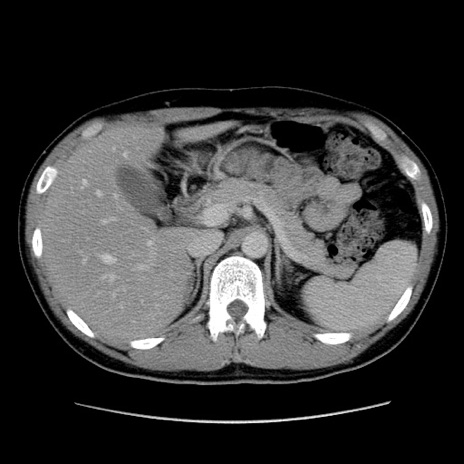

症例36(横断像)

【症例】20歳代 男性

【主訴】心窩部痛

【現病歴】今朝より上腹部痛あり。一旦軽快していたが再度出現したため救急要請。昨日夕に白身の魚を含む刺身を食べた。

【身体所見】BP 136/89mmHg、HR 74/min、BT 37.0℃、腹部:膨満、軟、心窩部に圧痛あり。反跳痛なし、筋性防御なし、腸雑音やや亢進あり。

【データ】WBC 17700、CRP 0.48